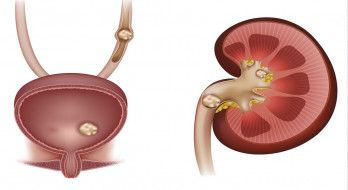

سنگ کلیه

سنگ کلیه تکه هایی مثل سنگ هستند که در یکی یا هر دوی کلیه ها می توانند به وجود آیند. نام پزشکی سنگ کلیه نفرولیتازیس است و اگر این بیماری باعث درد های شدیدی در بیمار شود (بیمار از شدت درد به خود بپیچد )...